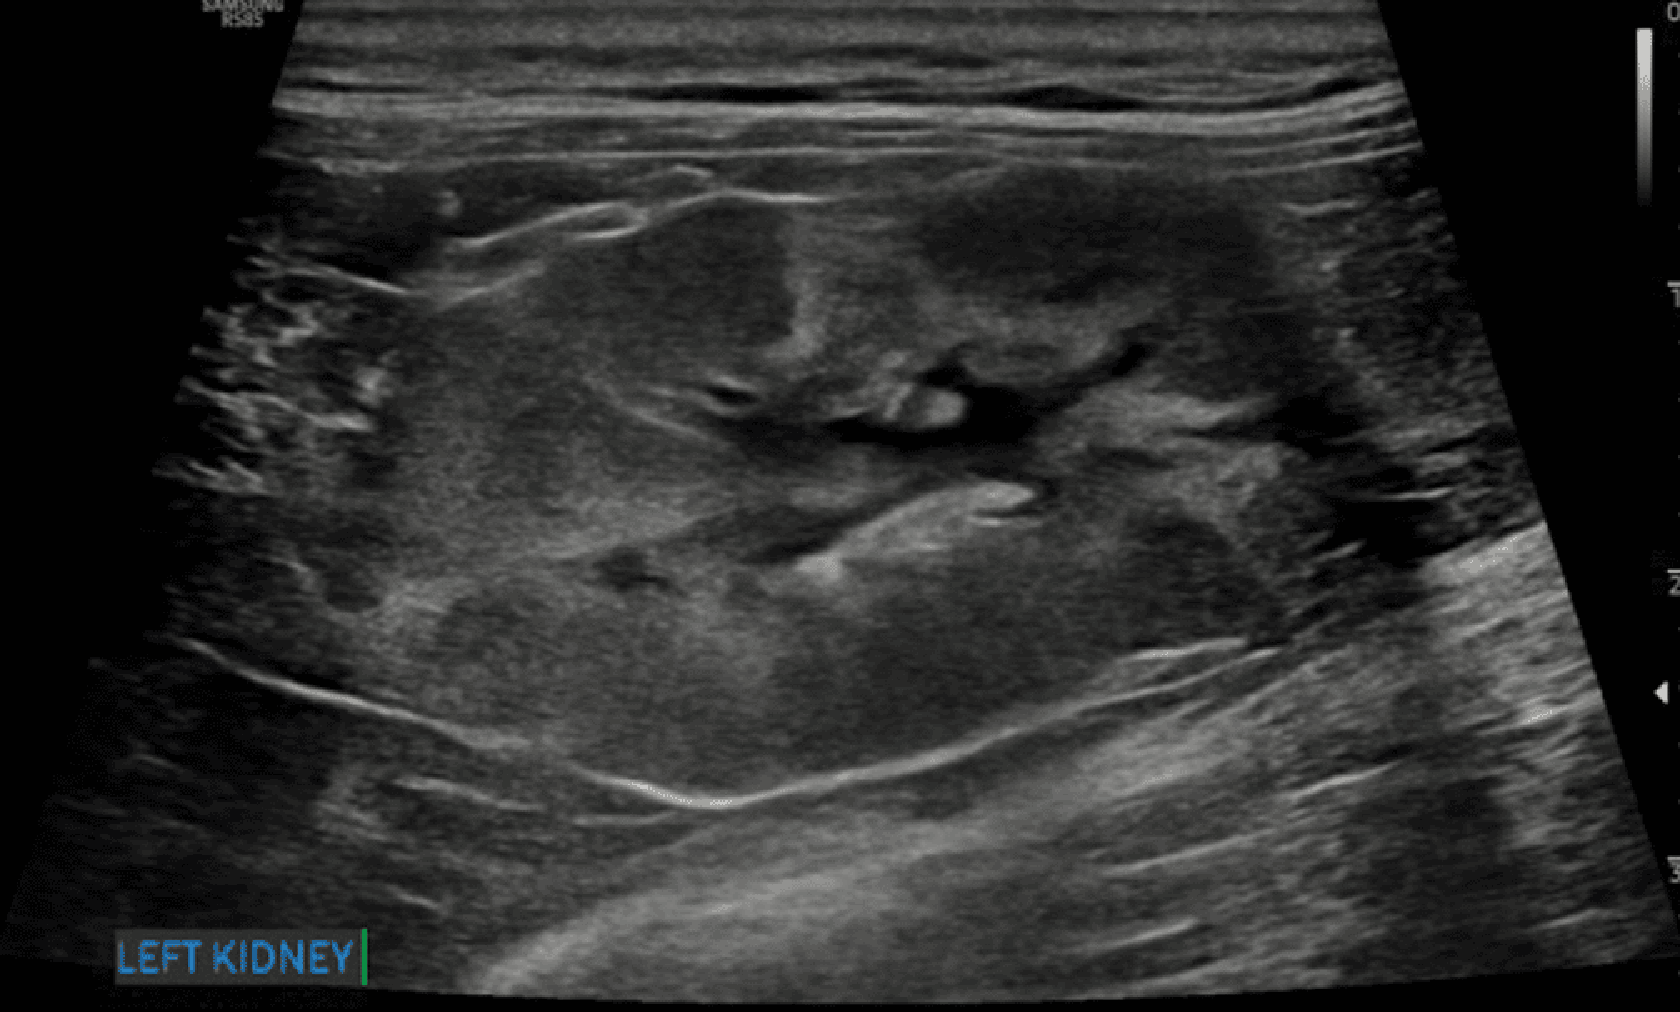

Nieregularny brzeg nerki

Nieregularne brzegi nerek (ryc. 9) mogą być związane z jednym lub kilkoma – często współwystępującymi – procesami, takimi jak zwłóknienie, stwardnienie, zanik, tworzenie torbieli albo zawał nerki.12 Nieregularny brzeg nerek jest często obserwowany w bardziej zaawansowanych stadiach przewlekłej choroby nerek i może wiązać się ze złym rokowaniem.8,15,17

Medium huguet ryc9 opt

Ryc. 9. Obraz w projekcji strzałkowej lewej nerki kota, ukazujący wyraźnie nieregularne brzegi związane z obecnością hiperechogeniczności kory nerki oraz przewlekłych zawałów kory nerkowej. Obecna jest także łagodna pielektazja.